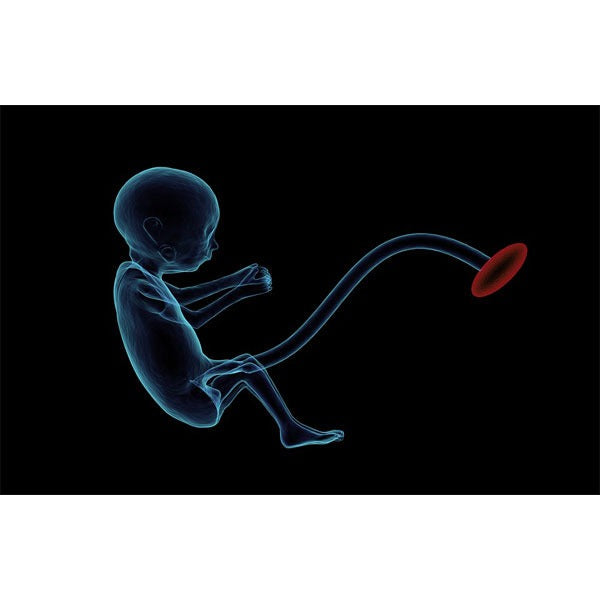

Potrivit IFL Science, oamenii de știință din cadrul Spitalului pentru Copii din Philadelphia au reușit performanța de a crea un uter artificial, care ar putea ține în viață bebelușii născuți inainte de termen. Invenția pare desprinsă dintr-un film science fiction: uterul artificial este format dintr-o pungă de plastic, umplută cu un lichid realizat în laborator (ce ține locul lichidului amniotic), la care sunt conectate diverse tuburi. Sistemul este conceput astfel încât să imite condițiile de dezvoltare din interiorul uterului uman. Dat fiind faptul că plămânii bebelușilor născuți prematur nu sunt dezvoltați într-atât încât să respire oxigen atomosferic, acest sistem îi ajută în procesul de dezvoltare a plămânilor.

Cum s-a procedat? În interiorul fiecărui bio-sac a fost plasat câte un miel, având vârsta echivalentă cu cea a unui fetus uman de 23 de săptămâni. Sistemul a fost unul inchis, steril. Cordonul ombilical al fetușilor a fost conectat la un sistem de oxigenare. Cercetătorii au convenit ca circuitul bio-sacului să fie unul fără pompă, astfel încât fluxul sanguin să fie condus numai de inima mieilor. Aceștia au fost ținuți în interiorul bio-sacilor timp de patru săptămâni, timp în care s-au dezvoltat normal.